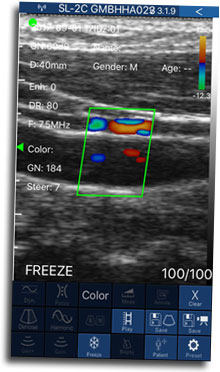

La finalidad de este reconocido curso internacional Hands On es poner al día los conceptos básicos de la Ecografía Doppler aplicados al estudio de la enfermedad venosa crónica y su utilización en la realización de distintos tratamientos endovasculares venosos.

Dirigido por el Dr. Jorge Alberto Segura, el CIED 2018 ya tiene fecha confirmada: la segunda edición del Curso Internacional de Eco Doppler color venoso de miembros inferiores se llevará a cabo el 28 y 29 de noviembre próximos en la Universidad de Belgrano, en Buenos Aires.

Dirigido por el prestigioso doctor Jorge Alberto Segura, reconocido académico y uno de los grandes especialistas en la materia, este segundo curso contará, como en su edición anterior, con relevantes disertantes invitados y con el auspicio de las empresas Karkaletsis Electromedicina, Laboratorio Cetus y Farmacia Paseo Mitre.